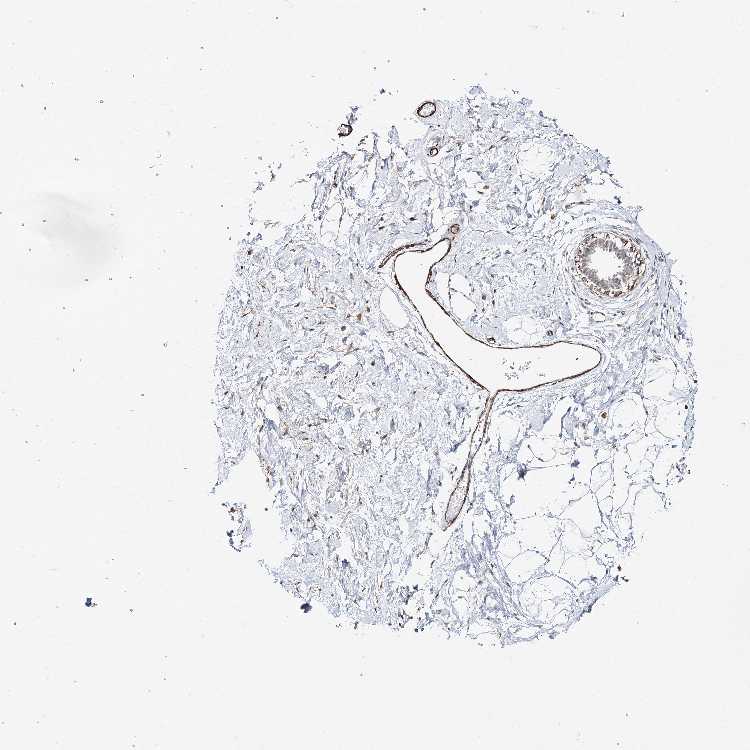

BREAST - Antibody stainingi

Antibody staining in the annotated cell types in the current human tissue is reported as not detected, low, medium, or high, based on conventional immunohistochemistry profiling in selected tissues. This score is based on the combination of the staining intensity and fraction of stained cells.

Each image is clickable and will lead to virtual microscopy that enables deeper exploration of all samples and also displays staining intensity scores, fraction scores and subcellular localization as well as patient and tissue information for each sample.

Antibody HPA037786Antibody HPA038034Antibody HPA038867Antibody HPA038868

Adipocytes Not detectedNot detectedNot detectedNot detected

Glandular cells LowHighNot detectedMedium

Myoepithelial cells LowMediumHighMedium